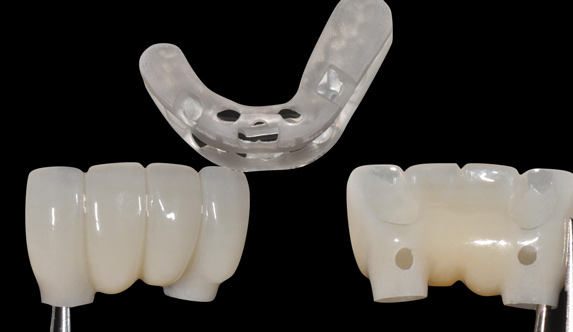

Fig 16. Presurgical design and fabrication of restorative components based on virtual implant position, allowing for possible minor angle/linear deviations (Fig 16 through Fig 18). Component options are broad and may include a custom healing abutment and bondable polymethyl methacrylate restoration; a single restoration with an engaging or non-engaging base; provisional fixed partial dentures (Fig 19), which can be indexed intraorally to prepared temporary abutments; or a full-arch restoration to be indexed intraorally to prepared temporary abutments.

Fig 17. Presurgical design and fabrication of restorative components based on virtual implant position, allowing for possible minor angle/linear deviations (Fig 16 through Fig 18). Component options are broad and may include a custom healing abutment and bondable polymethyl methacrylate restoration; a single restoration with an engaging or non-engaging base; provisional fixed partial dentures (Fig 19), which can be indexed intraorally to prepared temporary abutments; or a full-arch restoration to be indexed intraorally to prepared temporary abutments.

Fig 18. Presurgical design and fabrication of restorative components based on virtual implant position, allowing for possible minor angle/linear deviations (Fig 16 through Fig 18). Component options are broad and may include a custom healing abutment and bondable polymethyl methacrylate restoration; a single restoration with an engaging or non-engaging base; provisional fixed partial dentures (Fig 19), which can be indexed intraorally to prepared temporary abutments; or a full-arch restoration to be indexed intraorally to prepared temporary abutments.

Fig 19. Presurgical design and fabrication of restorative components based on virtual implant position, allowing for possible minor angle/linear deviations (Fig 16 through Fig 18). Component options are broad and may include a custom healing abutment and bondable polymethyl methacrylate restoration; a single restoration with an engaging or non-engaging base; provisional fixed partial dentures (Fig 19), which can be indexed intraorally to prepared temporary abutments; or a full-arch restoration to be indexed intraorally to prepared temporary abutments.